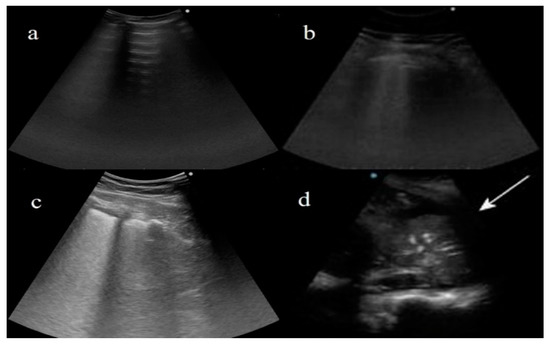

- Peng, Q.-Y.; Chinese Critical Care Ultrasound Study Group (CCUSG); Wang, X.-T.; Zhang, L.-N. Findings of lung ultrasonography of novel corona virus pneumonia during the 2019–2020 epidemic. Intensiv. Care Med. 2020, 46, 849–850. [Google Scholar] [CrossRef] [PubMed] [Green Version]

- Quarato, C.M.I.; Venuti, M.; Lacedonia, D.; Simeone, A.; Dimitri, L.M.C.; Rea, G.; Ferragalli, B.; Sperandeo, M. The Role of Transthoracic Ultrasound in the novel Coronavirus Disease (COVID-19): A Reappraisal. Information and Disinformation: Is There Still Place for a Scientific Debate? Front. Med. 2020, 7, 271. [Google Scholar] [CrossRef] [PubMed]